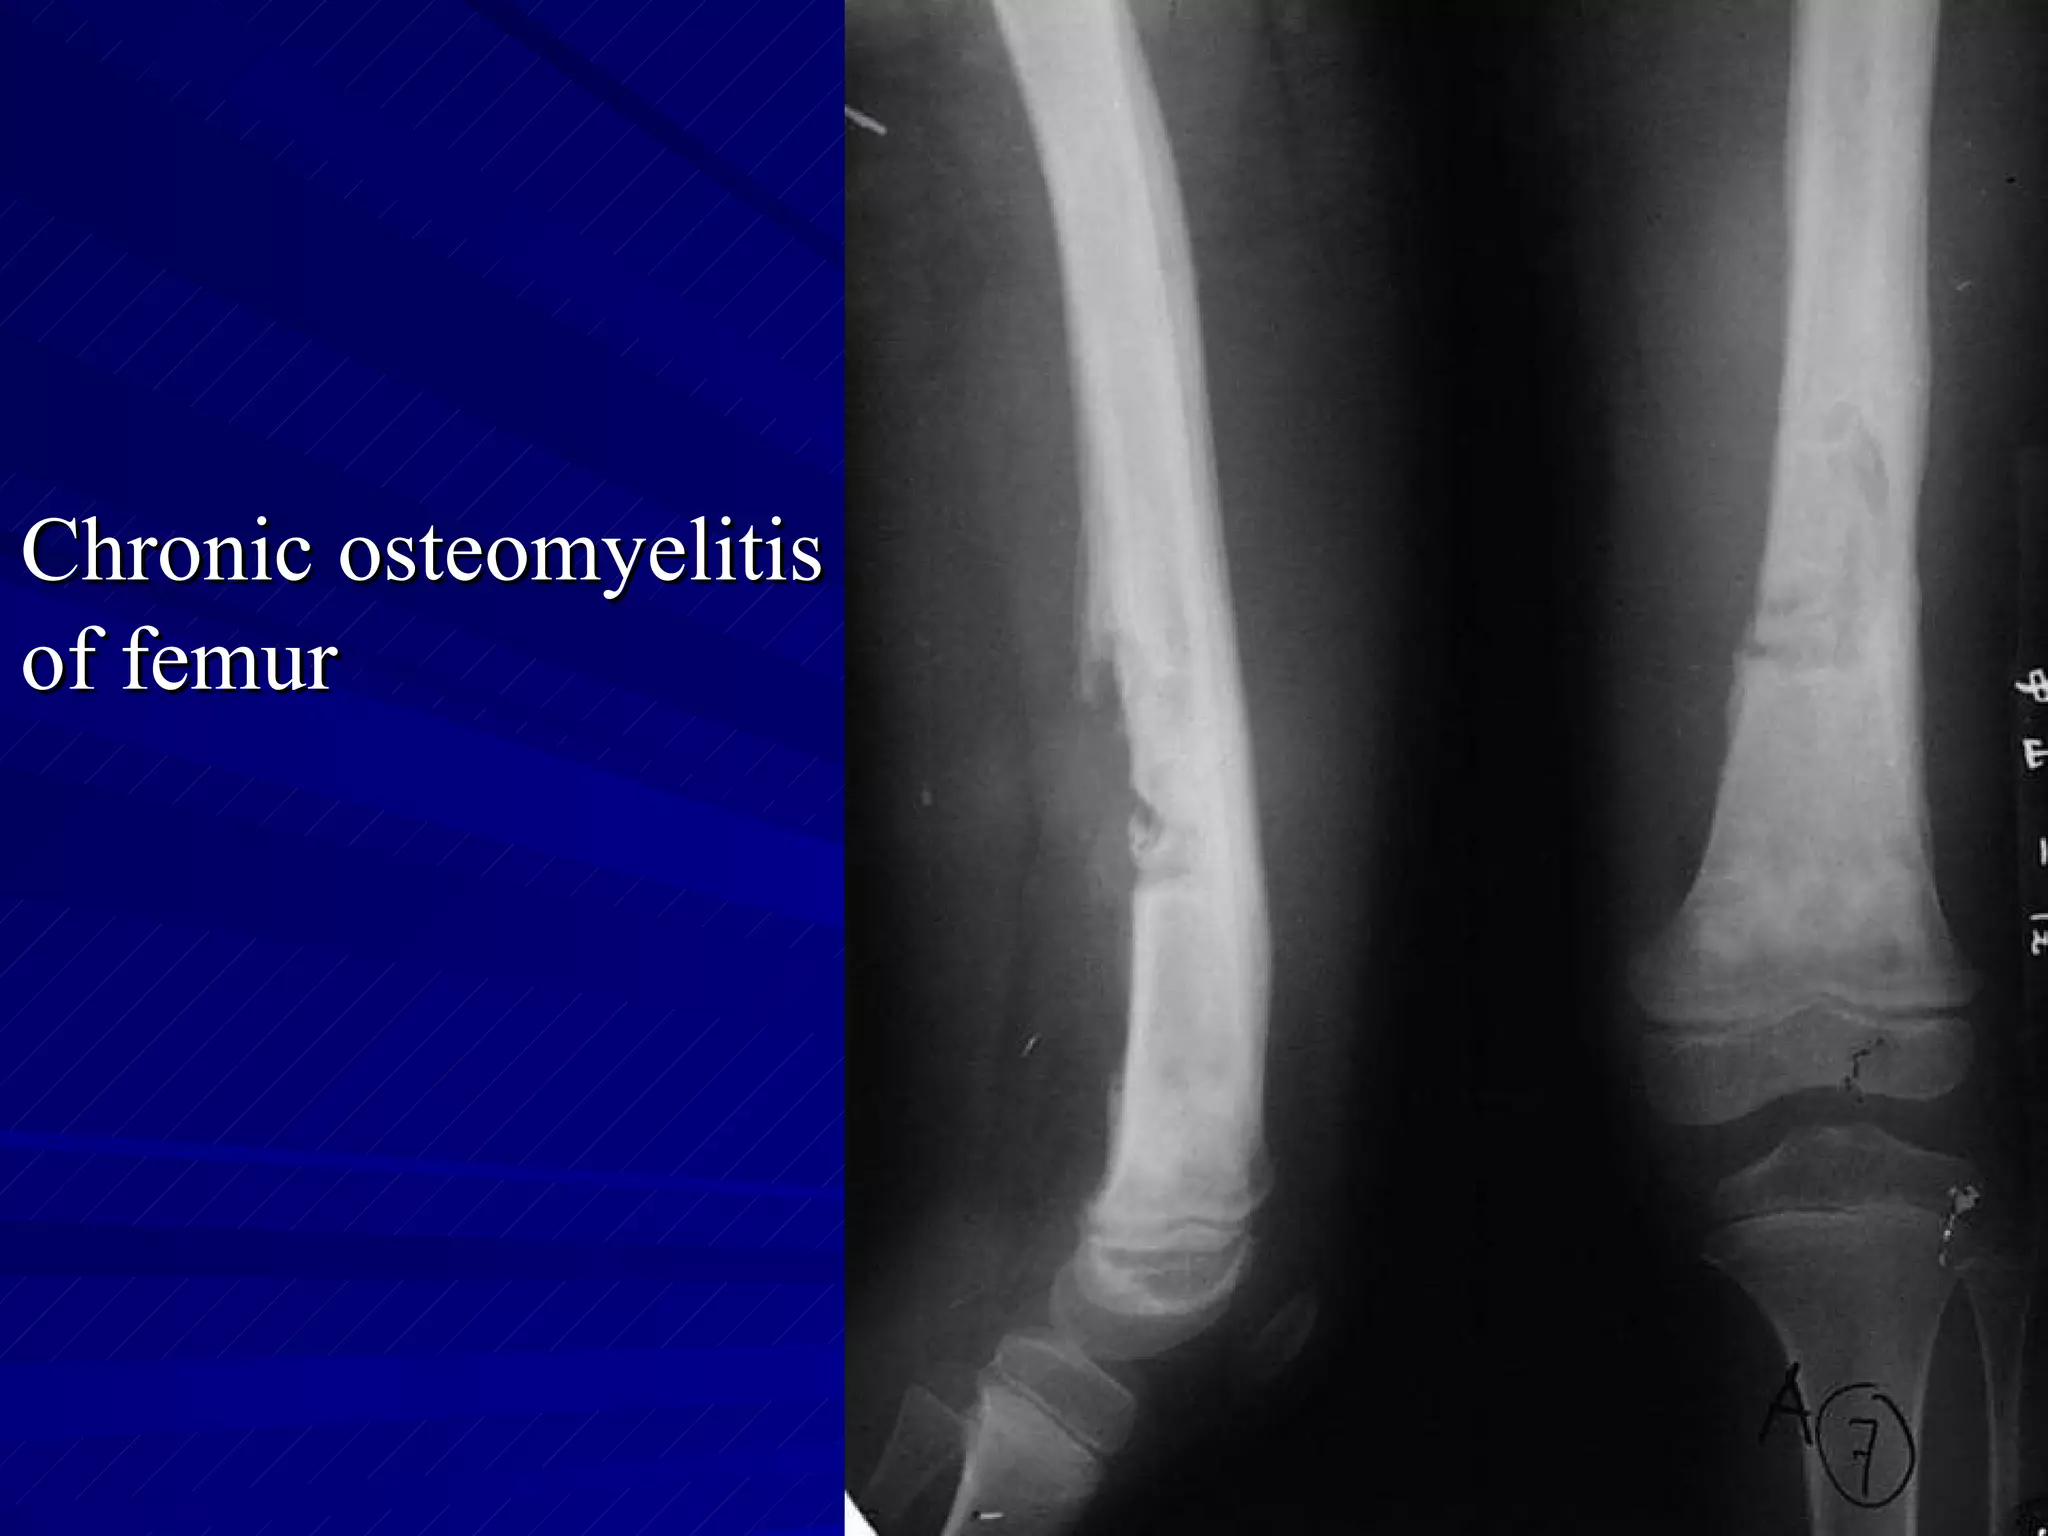

The document discusses various types of infectious diseases of bones and joints, including acute and chronic pyogenic osteomyelitis, Brodie's abscess, tuberculosis of long bones and the spine, and infectious arthritis. Specific examples provided include tuberculosis of the spine, hip, knee, and foot bones as well as pyogenic arthritis affecting the hip and knee joints. The document also mentions normal x-ray appearances of joints and basic features of joint diseases visible on x-rays such as swelling, destruction, degeneration, ankylosis, and dislocations.